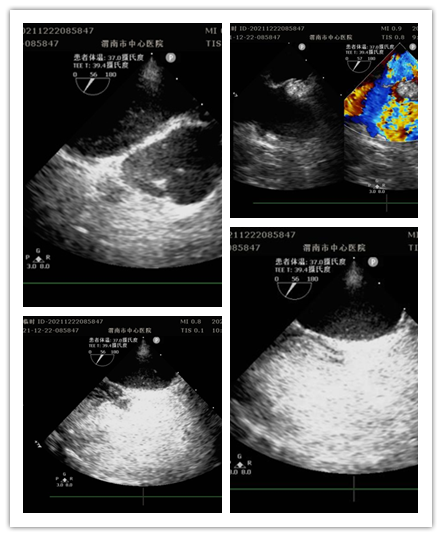

12月22日上午,开云在线登录超声科门诊完成全市首例经食管超声心动图。这是继完成30例术中经食管超声心动图之后首次在门诊进行。此项检查填补了渭南市超声诊疗空白,标志着医院心血管诊疗技术迈向新台阶。

患者女性,13岁,因间断眩晕1年,加重伴头痛20余天就诊于医院全科医学科。住院期间,行经胸超声右心声学造影提示存在心内分流,为进一步明确心脏疾病,行经食管超声心动图检查。检查前,超声科杨玉萍医师对患者充分评估,与刘晓晖主任共同商定患者检查方案,进行充分准备。为保障小患者安全,全科医学科副主任医师苗娟妮、心脏外科副主任姜永红及团队全程参与。在多名医护人员的通力协作下,成功为患者行经食管超声检查。检查过程顺利,患者无不良反应,最终明确超声诊断,为患者进一步治疗提供了有力依据。

经食管超声心动图检查是将超声探头插入食管,直接贴在心脏的后方,从后向前观察心脏、血管和血流动力学情况,避免了气体及脂肪的干扰。加之食道超声的探头频率高于普通经胸超声探头,所以能扩大心脏的扫查范围,提高图像质量及细微分辨率。主要运用于术前评估、术中监测、术后复查,尤其是对经胸超声心动图检查成像困难或有关结构显示不清,致使诊断难以明确的各种心脏或大血管疾病患者,能更加准确地诊断心脏细小病变及疑难疾病。特别是能有效评估房颤患者血栓形成的危险性并作为可靠依据,对房颤治疗前期评估具有重要意义。